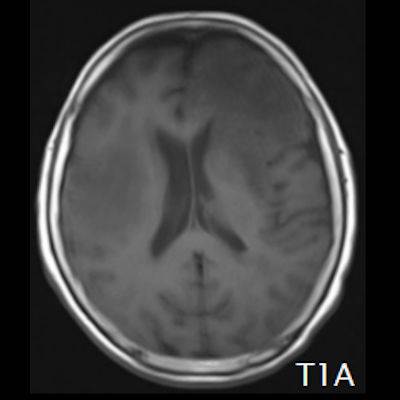

- (A) Her iki periventriküler beyaz cevherde aksiyel T2A, FLAIR serilerde hiperintens, T1A hipointens geniş ödem alanları (oklar) izlenmektedir. Sol frontalde T2A’da hipointens kitle lezyonuna (ok) dikkat ediniz.

- (C) Difüzyon ağırlıklı görüntülerde sol frontaldeki kitle lezyonunda difüzyon kısıtlama bulgusu (oklar) mevcut olup perfüzyon MRG’de rCBV haritasında belirgin perfüzyon artışı izlenmemektedir (ok).

- Genellikle supratentoriyal alanda, bazal ganglion, periventriküler beyaz cevher, orta hat ve korpus kallozum vb. yerleşme eğiliminde tek veya multipl kitleler şeklinde görülür.

- Kitleler çoğunlukla solid ve homojendir.